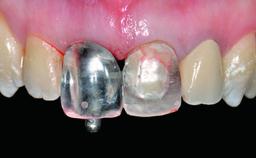

In 2008, a healthy 15-year-old female, non-smoking patient presented at our clinic with a major esthetic problem of tooth 21. Her dental history revealed that the tooth had been avulsed by trauma years before. As a result, the replanted and temporarily splinted tooth had ankylosed and was in severe apical malposition. The ankylosed tooth exhibited a significant gingival recession that disturbed the patient greatly. Due to the patient’s low age and with her skeletal growth not completed, periodic follow-up visits were scheduled to monitor the situation until the patient was old enough for implant therapy.

Placement Protocol Early or late implant placement

Bone Volume Deficient vertically or deficient vertically AND horizontally